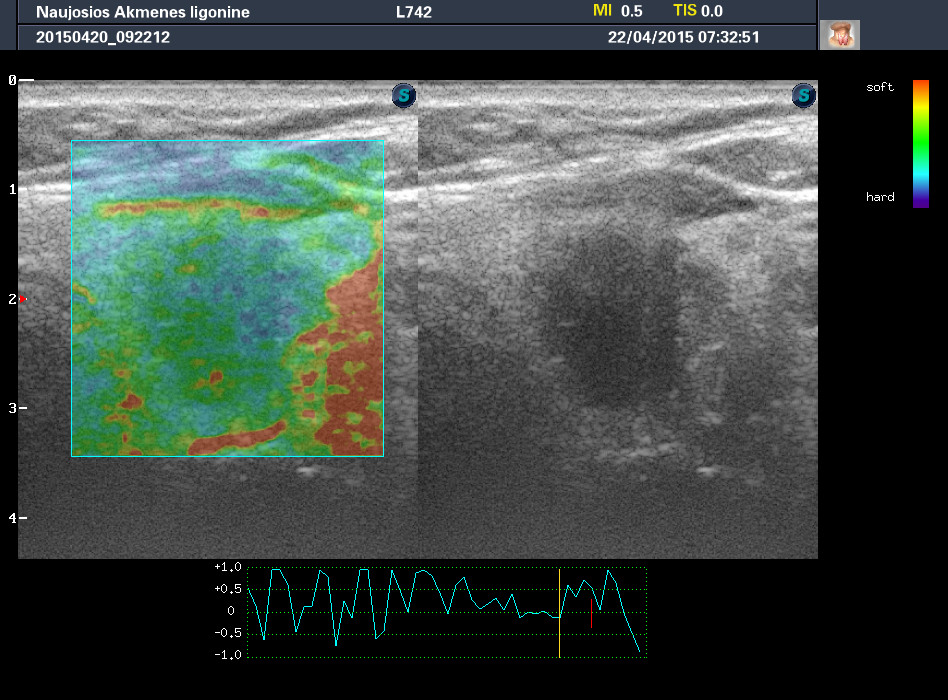

Случай 2

Женщина 61 год, жалоб нет. Рост узла за год +1 мм. Регионарные ЛУ не увеличены.

apr222015113257_27.jpg

apr222015113351_29.jpg

apr222015113413_30.jpg

1-й узел злокачественный, а 2-й ,скорее всего, доброкачественный. Но,понятное дело, нужна пункция и было бы здорово узнать результат.